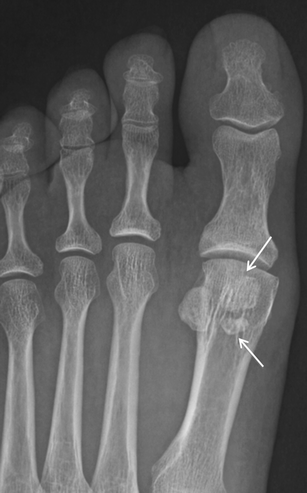

Bipartite lesser metatarsal sesamoid. Bipartite fifth metatarsal sesamoid is shown (arrow), with ell-corticated rounded fragments that do not fit together

Os intermetatarseum. Oblique radiographs of the foot from two different patients show rounded (a) and spindle (b) configurations of the os intermetatarseum (arrows) located between the base of the first and second metatarsals. This may sometimes be mistaken for a bone fragment secondary to a remote trauma